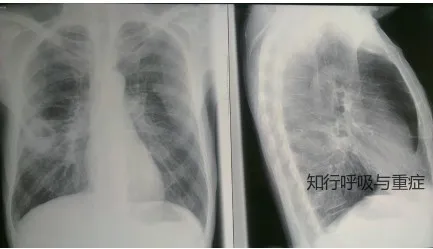

2)评估:胸部X线和CT扫描有助于诊断肺脓肿。

肺脓肿的CT扫描

肺脓肿与肺部囊性病变(如肺内支气管囊肿、肺隔离症或继发性感染的肺气肿性大疱)的鉴别有时较为困难。然而,病变的部位和临床表现通常能为诊断提供指导。局部性胸膜脓肿可通过CT扫描或超声进行区分。其中气-液平面的影像学表现也可见于肺部包虫囊肿。